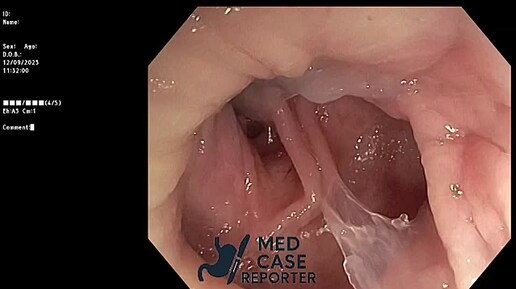

Несостоятельность анастомоза после передней резекции прямой кишки. Закрытие свища.